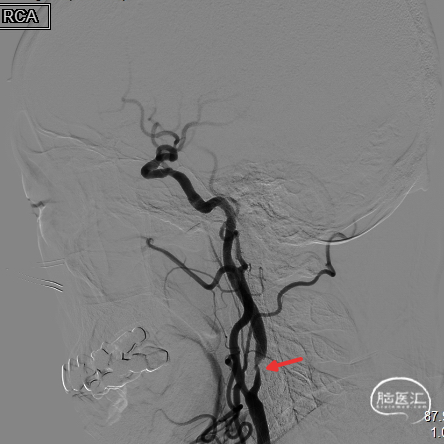

4.0*30mm通桥白驹®球囊以6atm扩张(左图箭头),扩张完毕后多角度造影显示狭窄交前明显改善(中图箭头处),扩张完毕后支架置入(右图箭头处)。